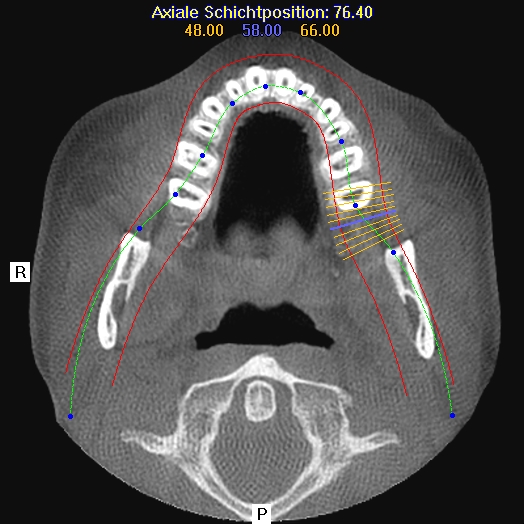

Im folgendem sehen Sie die Darstellung eines Teils des menschlichen Schädels mit Lokalisation des Nervkanales.

Querschnitt Unterkiefer |